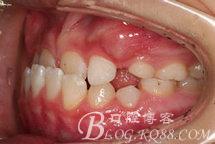

主訴:前牙反咬合(地包天)。曾經(jīng)有奶瓶喂養(yǎng)史。否認(rèn)家族遺史。

診 斷:安氏I類錯(cuò)合(III類傾向)。骨骼III類關(guān)系。凹面型:上頜劣生長、下頜過生長。上頜尖牙萌出間隙不足。前牙骨性反咬合。

兩個(gè)月后復(fù)診:下頜已被引導(dǎo)向后,11#牙與對頜的反咬合關(guān)系已經(jīng)解除,其余前牙呈對刃合。繼續(xù)戴用直到前牙呈比較大的覆蓋。然后換用上頜2x4固定矯治器。